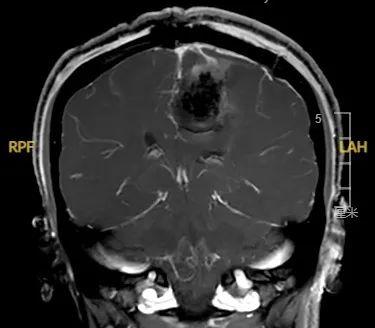

昆山市一医院神经外科成功切除颅内功能区巨大脑膜瘤

手术后

摘除“炸弹”,回归家庭